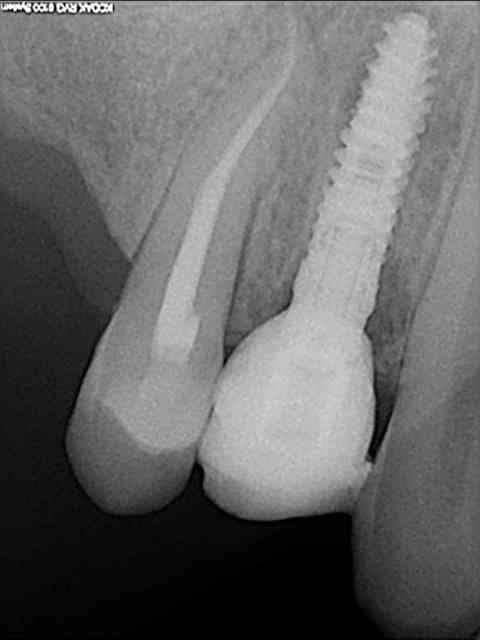

aussitôt demandé, aussitôt fait !!

(j+1 an)

tu as perdu pas mal d'os!!